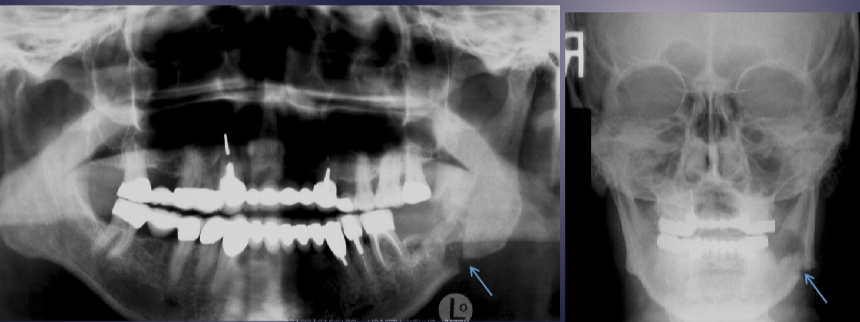

what are the arrows pointing to

“Halo sign”: elevation/displacement of max sinus floor

fistula due to acute osteomyelitis

what is the white arrow pointing to

periosteal reaction due to acute osteomyelitis

pathologic fracture of the L mandible due to acute osteomyelitis